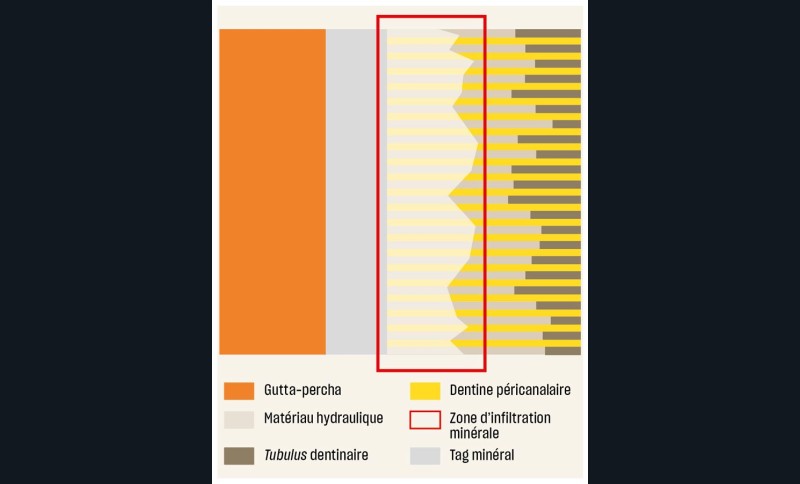

Ensuite, ces matériaux possèdent de réelles capacités d’adhésion à la dentine grâce à la formation de liaisons covalentes avec la dentine [41]. On observe également une zone d’infiltration minérale au niveau de l’interface dentine/matériau qui se prolonge par des « tags minéraux » dans les tubuli dentinaires [42], une sorte de « couche hybride minérale ». Il ne s’agit donc plus d’un simple scellement micromécanique mais bien d’une véritable adhésion physico-chimique garante d’une étanchéité pérenne (fig. 22). Cette étanchéité va d’ailleurs se bonifier avec le temps (à l’inverse de ce qui se passe avec les ciments de scellement) grâce aux échanges ioniques dent/matériau qui continuent bien après la prise [43].